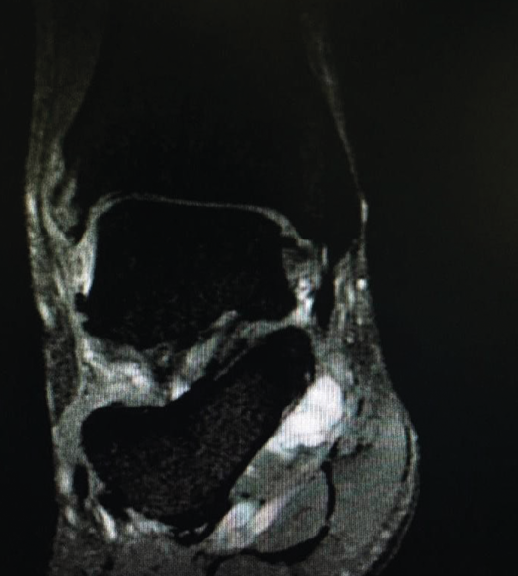

Figura 1. Resonancia magnética, corte coronal en T2. Se observa una lesión ocupante de espacio en el canal tarsiano.

Además, se evidenció el signo de Tinel positivo en el canal retromaleolar del tobillo derecho. La prueba de dorsiflexión-eversión fue positiva, reproduciendo la clínica. No se evidenció atrofia de la musculatura intrínseca plantar. El estudio radiológico simple descartó deformidades o lesiones óseas. La resonancia magnética (RM) objetiva la presencia de una imagen de contenido líquido en el canal tarsiano, compatible con un quiste sinovial o ganglión (Figura 1). El estudio neurofisiológico, mediante electroneurografía y electromiografía, mostró disminución de la velocidad de conducción sensitiva, con afectación de las ramas plantar medial y lateral del nervio tibial posterior derecho (Figura 2 y Tabla 1).